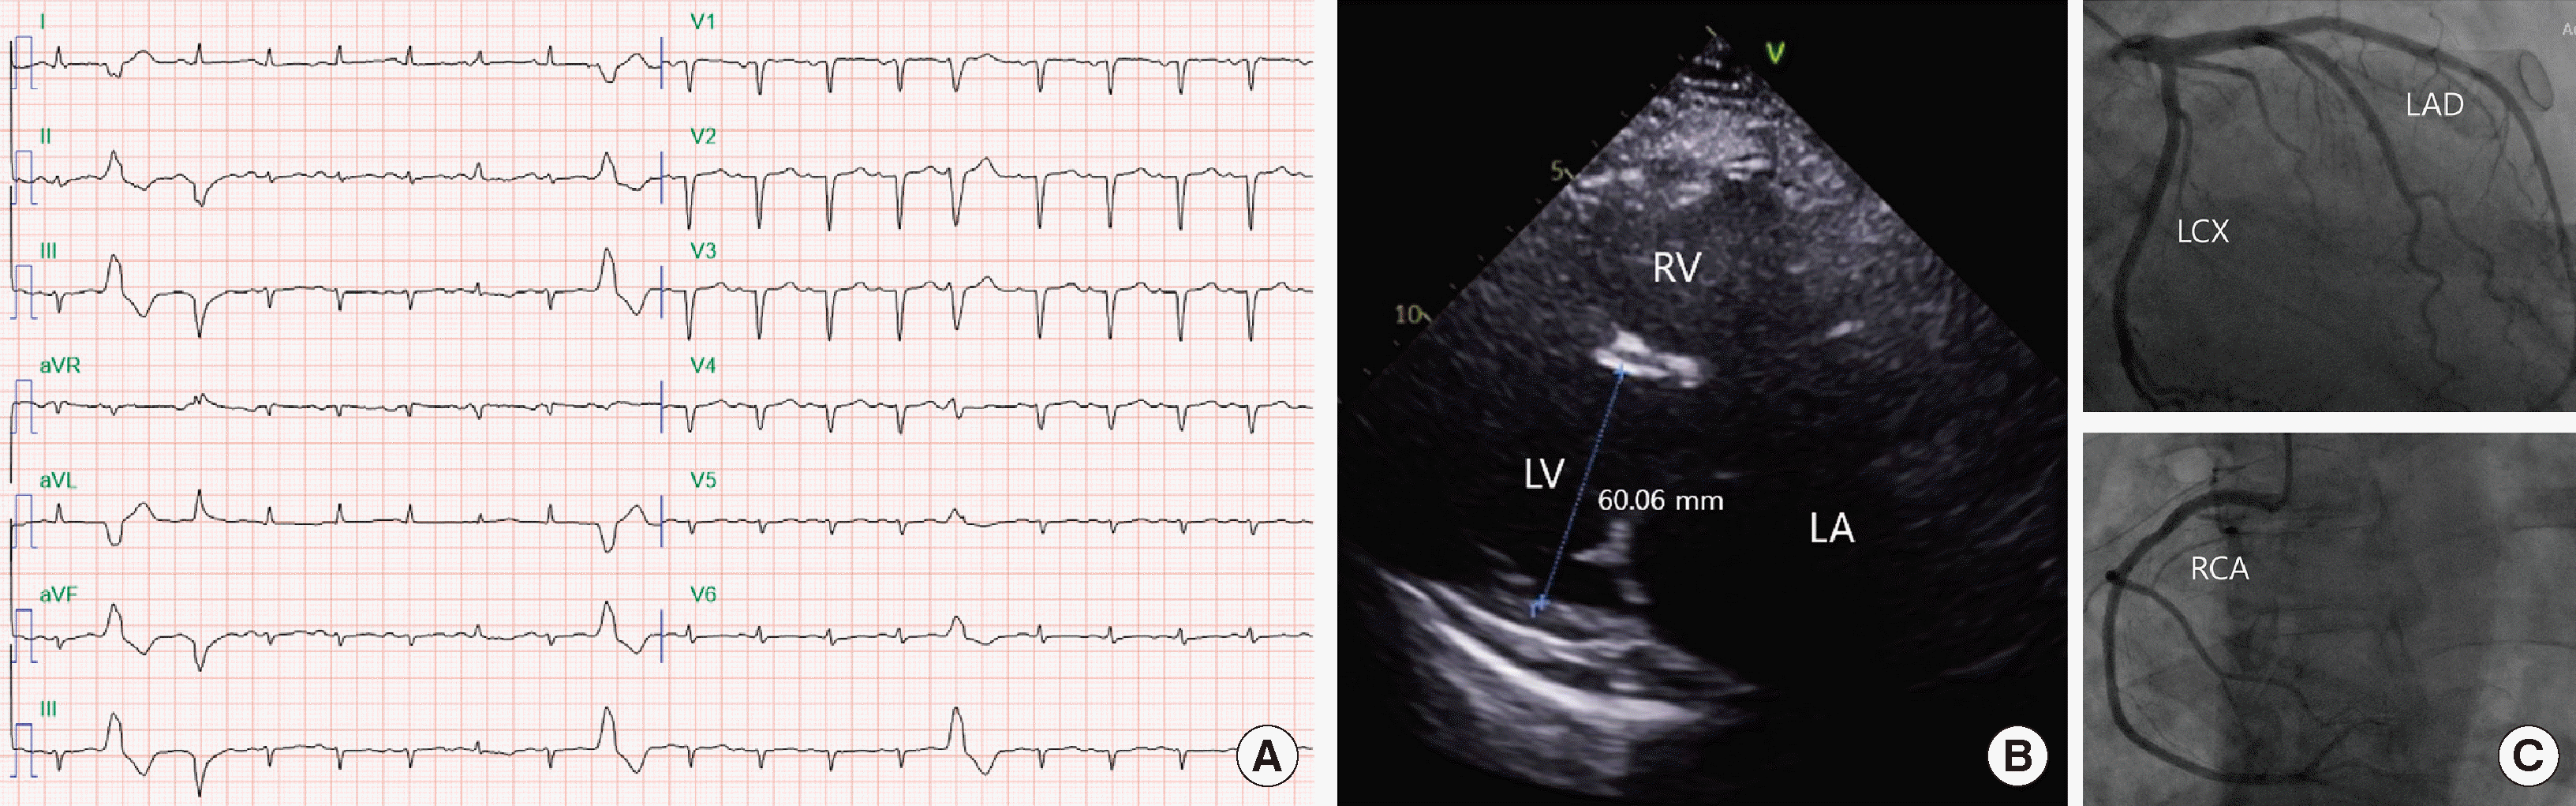

A 51-year-old woman presented with dyspnea on exertion and a 20 kg weight gain over the previous three months. Physical examination revealed signs of heart failure, including peripheral edema and abdominal distention. Laboratory tests showed significantly elevated N-terminal pro B-type natriuretic peptide (NT-proBNP) levels (2,426.0 pg/mL), indicating severe heart failure. The electrocardiogram showed sinus tachycardia and multiple ventricular premature complexes (Fig. 1A). Transthoracic echocardiography revealed severe left ventricular systolic dysfunction with an ejection fraction of 23.2% and left ventricular enlargement with normal wall thickness, consistent with a diagnosis of DCM (Fig. 1B). Coronary angiography revealed no significant atherosclerosis, ruling out ischemic causes for the DCM (Fig. 1C).

Fig. 1

(A) Electrocardiogram showing sinus tachycardia and multiple ventricular premature complexes. (B) Echocardiogram showing a dilated left ventricle with a 60.06 mm left ventricle dimension. (C) Coronary angiogram showing insignificant stenosis of the LAD, LCX, and RCA. Abbreviations: LAD, left anterior descending artery; LCX, left circumflex artery; RCA, right coronary artery.